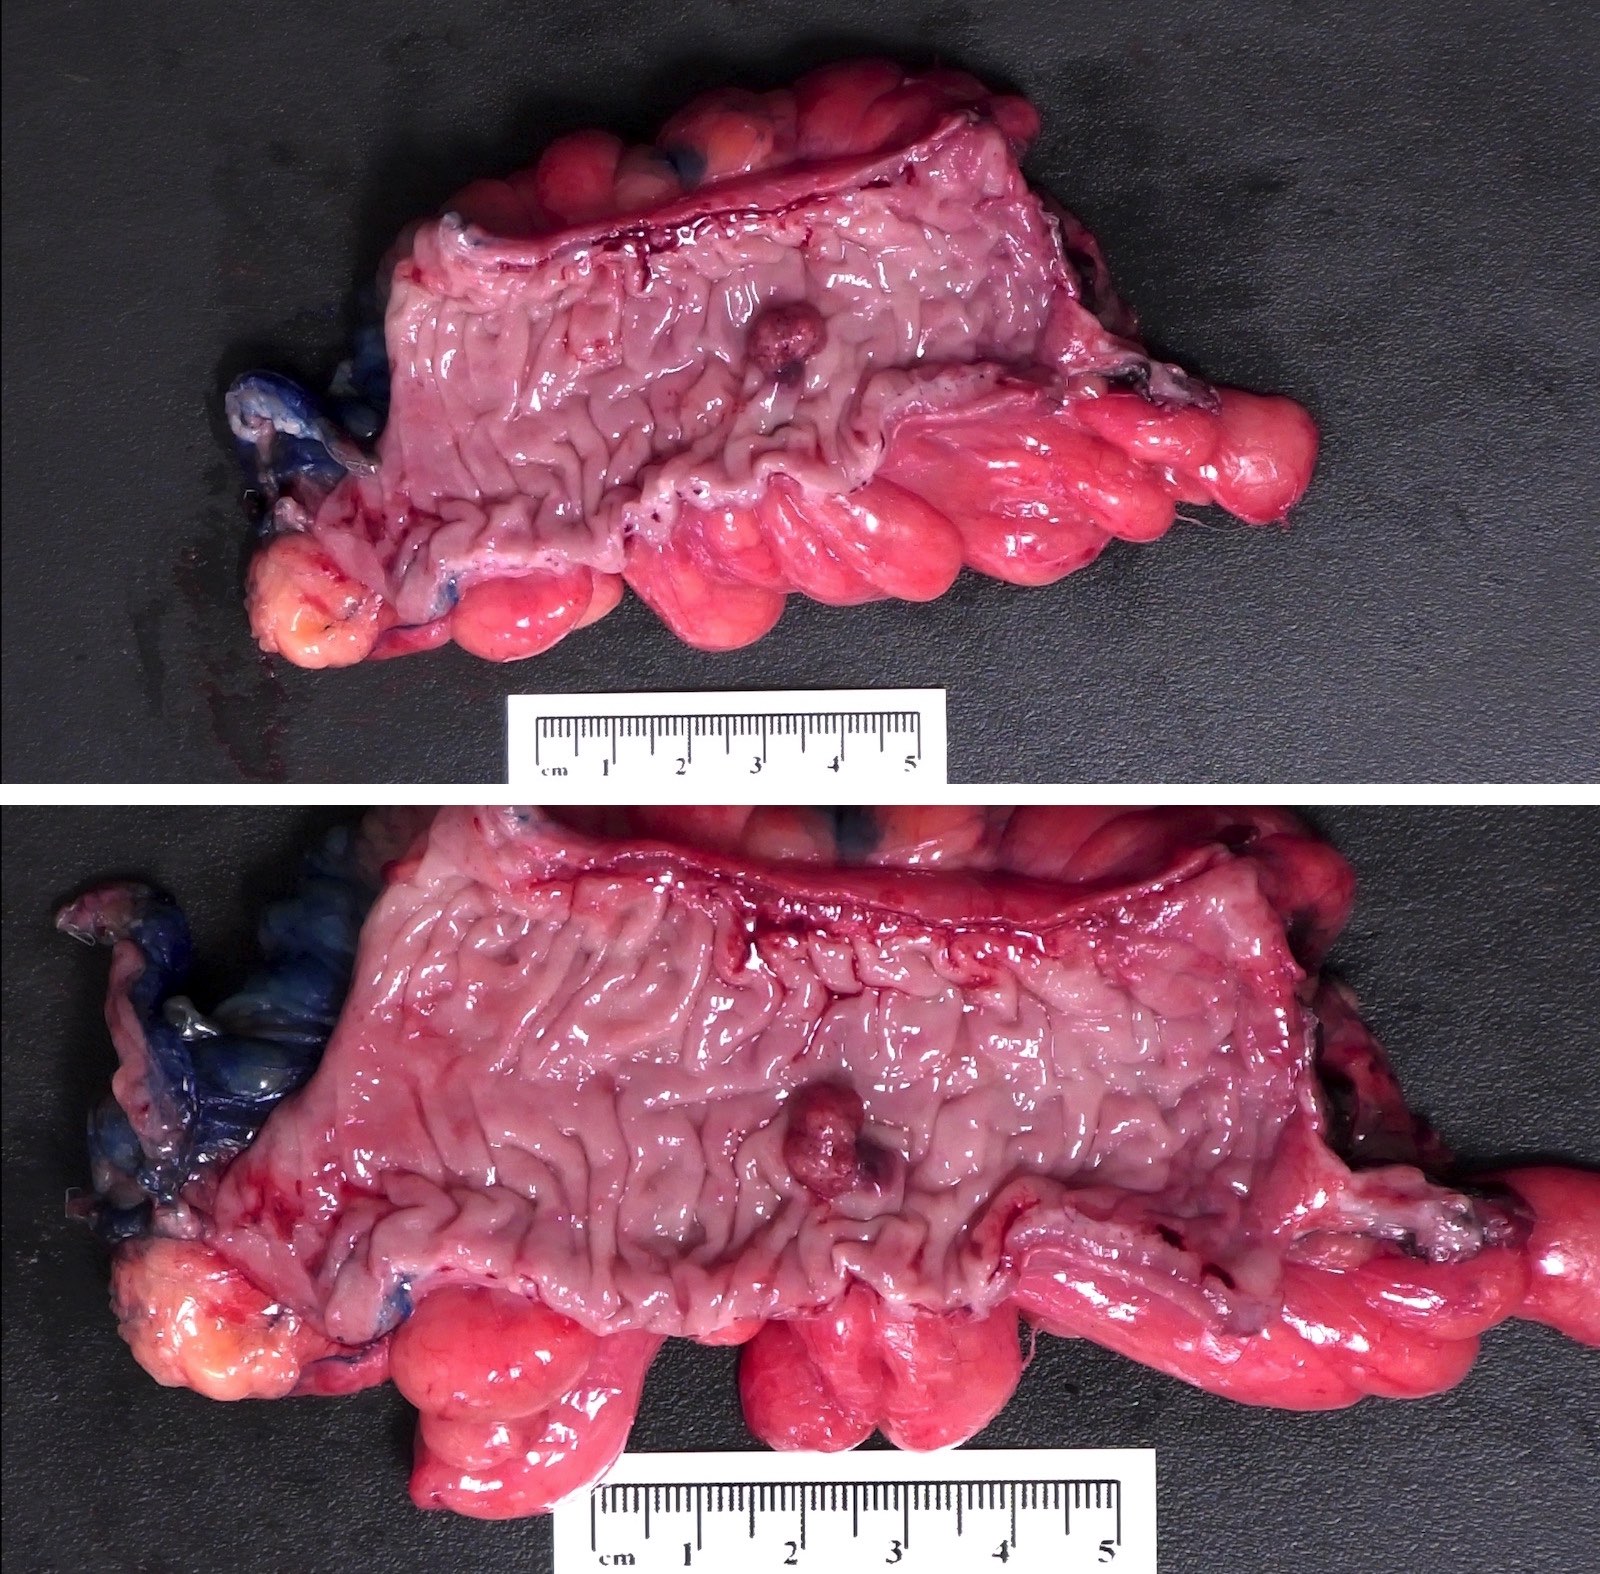

Gross description

- May be sessile or pedunculated

- Typically dark red compared with mucosa

- Features concerning for high grade dysplasia or malignancy include size > 1 cm, villous architecture and ulceration / friability

Gross images